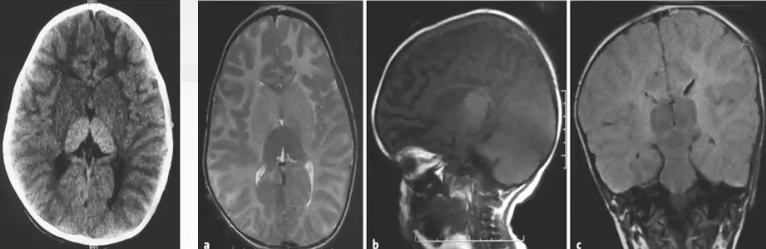

Sandhoffs病

❖ GM2神经节苷脂沉积病的Ⅱ型,即急性早期婴儿型

❖ CT表现为双侧丘脑对称性高密度。

❖ MRI表现为双侧丘脑T1高信号,T2低信号伴有白质高信号。